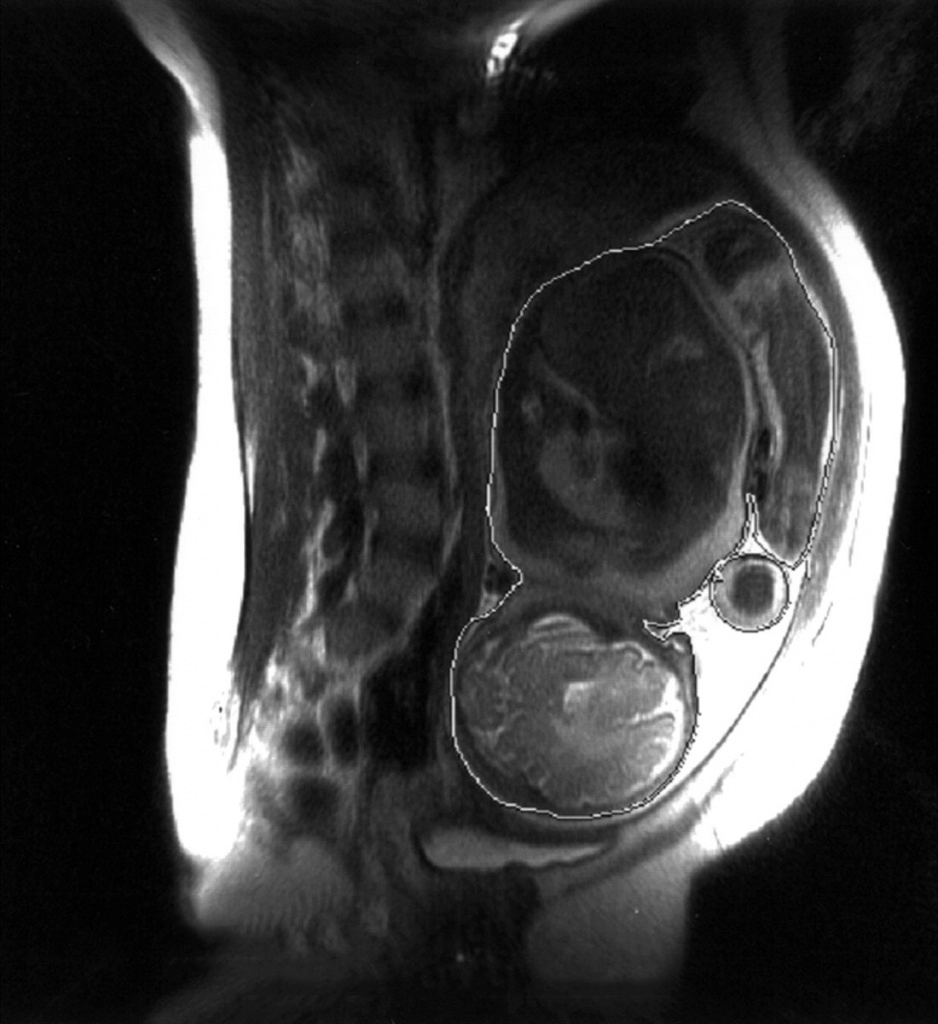

• До 220 кг

КТ при беременностиНесмотря на существенное снижение лучевой нагрузки на организм пациента, достигнутое при использовании современных моделей томографа, КТ при беременности остается достаточно небезопасной процедурой. Основная сложность заключается в том, что рентгеновское излучение является мощным мутагенным фактором, способным оказать сильное негативное влияние на развитие плода. Поэтому исследование назначают лишь в тех случаях, когда отказ от диагностики создает угрозу жизни женщины. Если же непосредственной опасности нет, то врачи стараются обойтись другими, менее опасными инструментальными методами – УЗИ либо МРТ. Необходимо веское обоснование для назначения компьютерной томографии беременной женщине.

Наибольшую опасность радиологические исследования представляют в первом триместре вынашивания. После 15 недель влияние излучения становится не настолько сильным, хотя и в это время подвергать плод воздействию рентгеновских лучей нежелательно.

Состояние беременности само по себе является противопоказанием для любых процедур, связанных с воздействием жесткого излучения. Однако существенную роль играет область воздействия: если исследование головы, шеи, грудной клетки и конечностей при определенных условиях еще можно допустить, то облучение брюшной полости и малого таза исключено, если есть шанс сохранить жизнь женщины без этого исследования. Кроме того, имеет значение срок вынашивания:

Установлено, что уровень излучения, гарантированно не приводящий к появлению пороков развития плода, не должен превышать 1 мкЗв. Во время компьютерной томографии органов брюшной полости показатель облучения составляет 10-11 мкЗв. Поэтому при отсутствии жизненно важных показаний от этого исследования следует отказаться.

Клиника «Медицина» использует для проведения КТ беременным женщинам современные томографы Revolution CT либо Somatom Definition. Они используют мультиспиральную технологию сканирования, благодаря чему лучевая нагрузка на организм пациента снижается в несколько раз, при этом качество изображения существенно возрастает по сравнению с установками предыдущих поколений. Кроме того, увеличенный диаметр тоннеля не создает проблем при прохождении обследования даже на последних месяцах вынашивания.